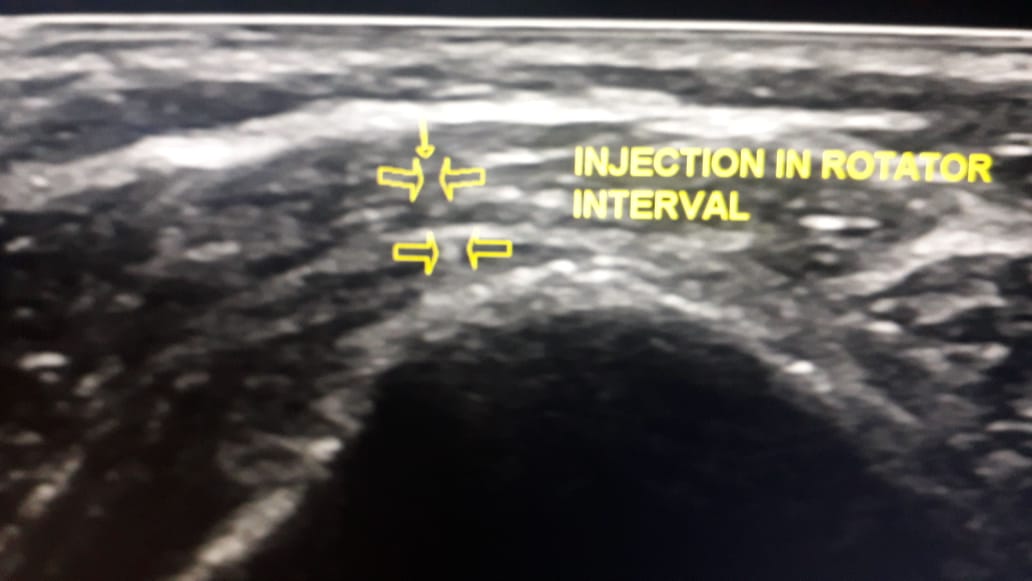

ultrasound guided injection in the rotator interval of shoulder joint (indication : frozen shoulder)

ultrasound guided injection in the rotator interval of shoulder joint (indication : frozen shoulder) ..